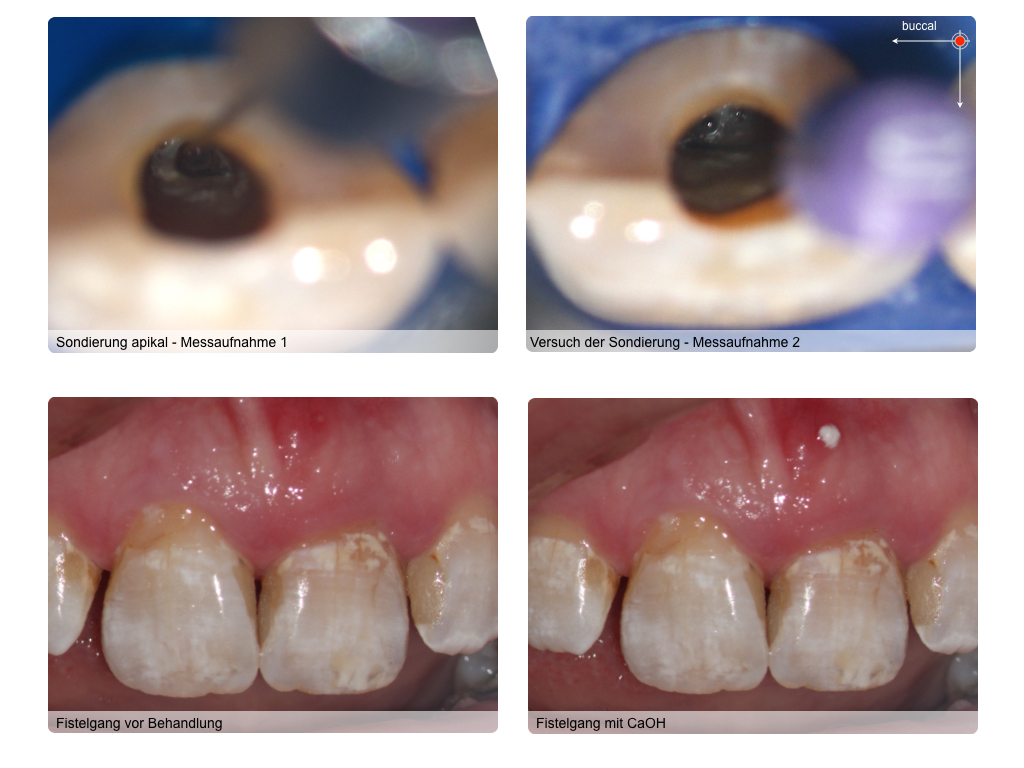

Lateraler Kanal (2)